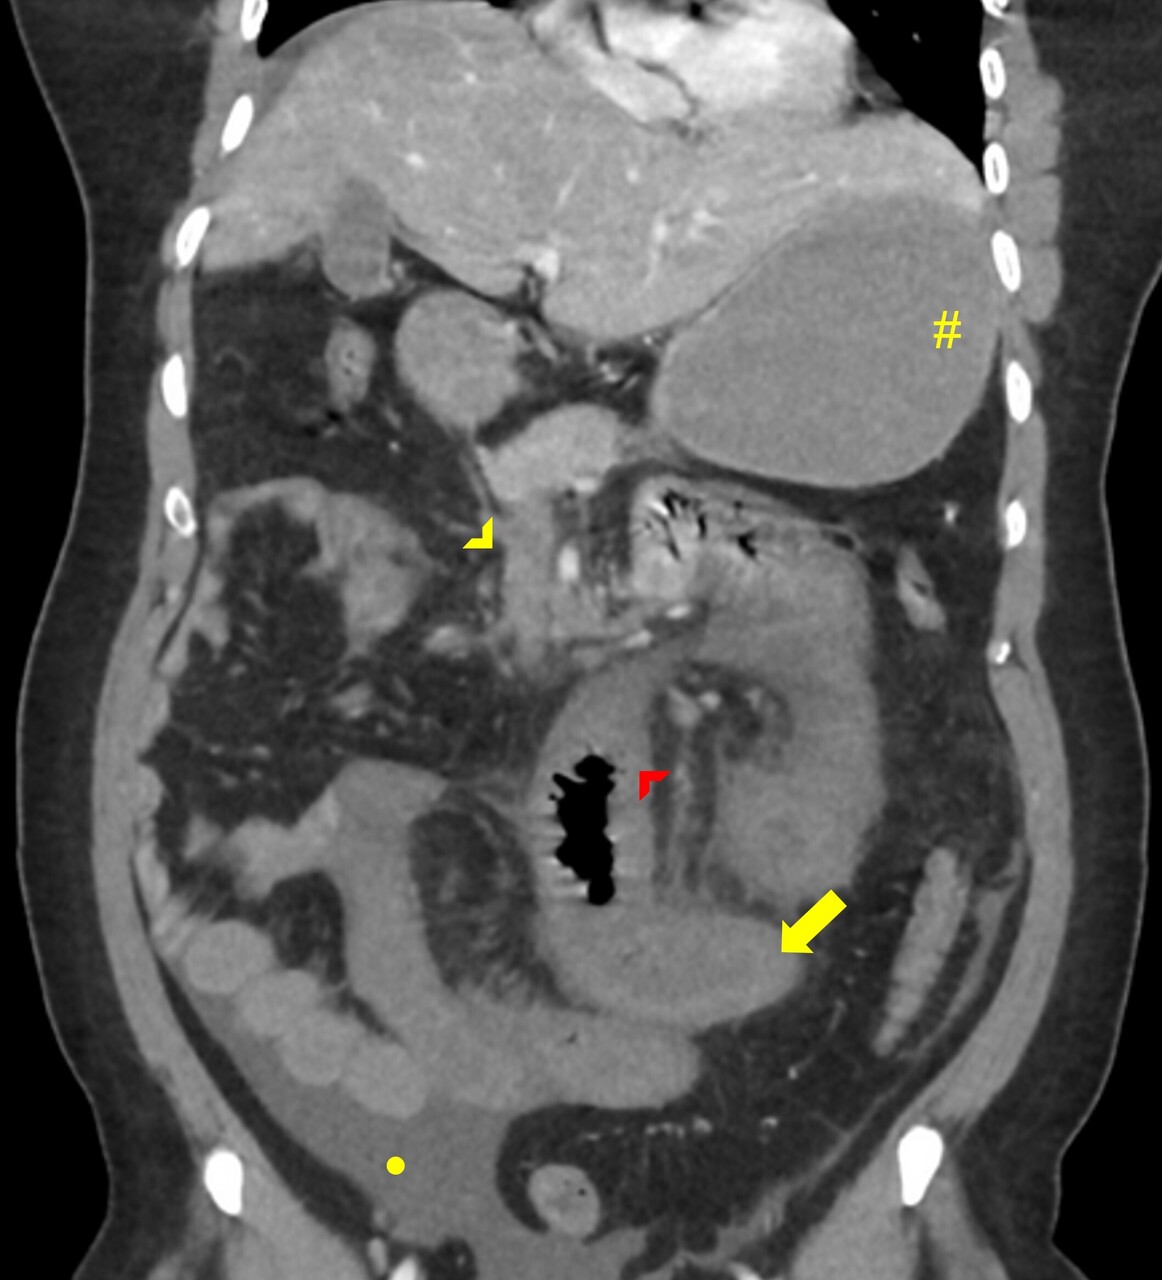

Le diagnostic de TVP récente repose sur l’imagerie. Elle doit être réalisée chez tout patient qui en présente une suspicion clinique. L’échographie-Doppler est généralement l’examen de première intention  ; elle permet la visualisation directe du thrombus dans la veine porte et l’absence de flux au Doppler en cas de TVP complète (sensibilité de 88 à 98  %, spécificité de 80 à 100  %). Elle doit être complétée systématiquement par un scanner (ou une imagerie par résonance magnétique [IRM]) abdominal avec injection de produit de contraste, et aux quatre temps d’acquisition (sans injection, phase artérielle, portale et tardive), si cette imagerie n’a pas été réalisée d’emblée. Le scanner permet de confirmer le diagnostic de TVP, de déterminer le degré d’extension aux veines spléniques et mésentériques, de rechercher un facteur local et des signes d’ischémie mésentérique. De plus, il permet d’identifier des signes d’hépatopathie chronique sous-jacente (dysmorphie hépatique, signes d’hypertension portale) [fig. 2].

Pour la TVP chronique sans hépatopathie chronique sous-jacente, la recanalisation de la veine porte par voie radiologique doit être envisagée en cas de complications réfractaires au traitement médical, comme des hémorragies digestives liées à l’hypertension portale non contrôlées par un traitement endoscopique, ou en cas de cholangiopathie portale symptomatique (fig. 4). La recanalisation portale s’effectue par la pose d’un stent dans la veine porte  ; elle peut être associée à la pose d’un TIPS (transjugular intrahepatic portosystemic shunt) L’abord peut être transhépatique, transsplénique ou transmésentérique. Cette procédure de radiologie interventionnelle est complexe et nécessite une prise en charge multidisciplinaire dans un centre expert, ce qui permet d’obtenir un succès technique de 80  % environ, mais au prix d’un taux de complications d’environ 20  %.21,22

Une ischémie mésentérique est recherchée systématiquement sur le scanner abdominal aux quatre temps (sans injection, temps artériel, portal et tardif) et est confirmée par la constatation de signes de souffrance intestinale associés à la TVP tels qu’un épaississement de la paroi intestinale et/ou une diminution de rehaussement des anses après injection de produit de de contraste. La mise en évidence d’une absence de rehaussement pariétal, d’une dilatation intestinale supérieure à 25 mm ou encore d’une pneumatose intestinale voire aéroportie (présence de gaz dans la lumière de la veine porte) sont des signes de gravité évoquant une nécrose intestinale et indiquant un traitement chirurgical.